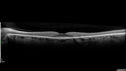

51 year old female on with trouble driving at night for a year. No eye examination for several years. 2009 (11 years ago) Plaquenil 300 then up to 400 a few years ago now down to 300 - 5'2" 135 lbs

VA 20/20 OD, 20/25 OS